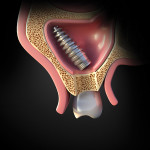

In 2013, the patient presented with the chief complaint of a loose restoration and pain in the maxillary left posterior area. When an orthopantomogram (OPG) was taken, the implant and permanent abutment at the site of tooth No. 14 was found to be displaced into the maxillary sinus (Figure 1). The patient was informed of the problem and advised of the potential complications if the implant/abutment was not removed. He then consented verbally and in writing to its removal after a discussion with the clinician of the risks and possible complications of the measures needed to be taken to perform this procedure.

Using the OPG of the sinus, the clinician examined the site of displacement and detected the implant/abutment and determined it to be apically located. The patient was asked to move his head in different directions. Two successive OPG images were then taken to determine that the implant/abutment was not attached to the sinus wall or located close to the ostium; this was apparent because the implant/abutment position changed when the patient moved his head in various directions (Figure 2). It was then decided to retrieve the implant/abutment from the sinus by using a lateral window approach.